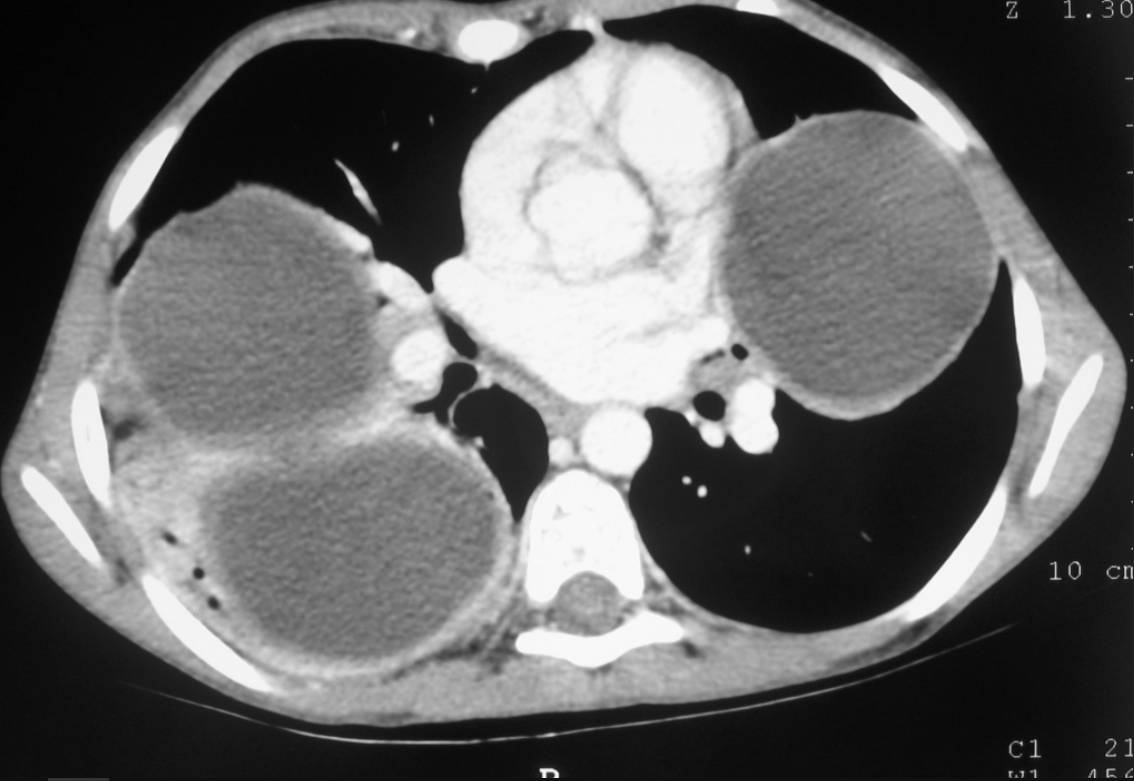

Chest X-ray revealed two nodular opacities (fluid density lesions) in right lung and one in left lung.

Thorax CT revealed two cysts in right lower and medium lobe of lung and one cyst in lingual lobe of left lung. The diagnosis of hydatid cysts was confirmed at surgery.

Imaging appearances may vary due to the growth of the parasite and its relationship to adjacent lung tissue. Initially, lung HC generally manifest as type I cysts, being oval or round and having well-defined borders. CT reveals the hypoattenuating nature of these lesions.